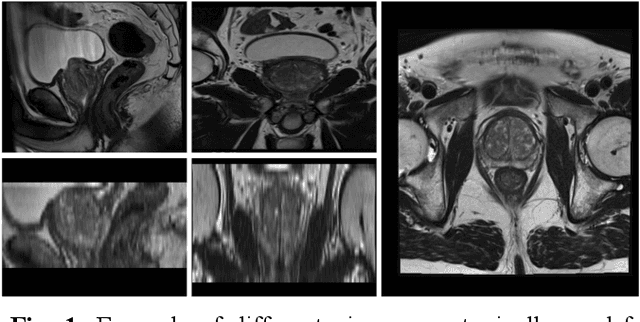

Abstract:Magnetic resonance imaging has evolved as a key component for prostate cancer (PCa) detection, substantially increasing the radiologist workload. Artificial intelligence (AI) systems can support radiological assessment by segmenting and classifying lesions in clinically significant (csPCa) and non-clinically significant (ncsPCa). Commonly, AI systems for PCa detection involve an automatic prostate segmentation followed by the lesion detection using the extracted prostate. However, evaluation reports are typically presented in terms of detection under the assumption of the availability of a highly accurate segmentation and an idealistic scenario, omitting the propagation of errors between modules. For that purpose, we evaluate the effect of two different segmentation networks (s1 and s2) with heterogeneous performances in the detection stage and compare it with an idealistic setting (s1:89.90+-2.23 vs 88.97+-3.06 ncsPCa, P<.001, 89.30+-4.07 and 88.12+-2.71 csPCa, P<.001). Our results depict the relevance of a holistic evaluation, accounting for all the sub-modules involved in the system.

Abstract:An accurate prostate delineation and volume characterization can support the clinical assessment of prostate cancer. A large amount of automatic prostate segmentation tools consider exclusively the axial MRI direction in spite of the availability as per acquisition protocols of multi-view data. Further, when multi-view data is exploited, manual annotations and availability at test time for all the views is commonly assumed. In this work, we explore a contrastive approach at training time to leverage multi-view data without annotations and provide flexibility at deployment time in the event of missing views. We propose a triplet encoder and single decoder network based on U-Net, tU-Net (triplet U-Net). Our proposed architecture is able to exploit non-annotated sagittal and coronal views via contrastive learning to improve the segmentation from a volumetric perspective. For that purpose, we introduce the concept of inter-view similarity in the latent space. To guide the training, we combine a dice score loss calculated with respect to the axial view and its manual annotations together with a multi-view contrastive loss. tU-Net shows statistical improvement in dice score coefficient (DSC) with respect to only axial view (91.25+-0.52% compared to 86.40+-1.50%,P<.001). Sensitivity analysis reveals the volumetric positive impact of the contrastive loss when paired with tU-Net (2.85+-1.34% compared to 3.81+-1.88%,P<.001). Further, our approach shows good external volumetric generalization in an in-house dataset when tested with multi-view data (2.76+-1.89% compared to 3.92+-3.31%,P=.002), showing the feasibility of exploiting non-annotated multi-view data through contrastive learning whilst providing flexibility at deployment in the event of missing views.

Abstract:Background: Prostate cancer (PC) MRI-based risk calculators are commonly based on biological (e.g. PSA), MRI markers (e.g. volume), and patient age. Whilst patient age measures the amount of years an individual has existed, biological age (BA) might better reflect the physiology of an individual. However, surrogates from prostate MRI and linkage with clinically significant PC (csPC) remain to be explored. Purpose: To obtain and evaluate Prostate Age Gap (PAG) as an MRI marker tool for csPC risk. Study type: Retrospective. Population: A total of 7243 prostate MRI slices from 468 participants who had undergone prostate biopsies. A deep learning model was trained on 3223 MRI slices cropped around the gland from 81 low-grade PC (ncsPC, Gleason score <=6) and 131 negative cases and tested on the remaining 256 participants. Assessment: Chronological age was defined as the age of the participant at the time of the visit and used to train the deep learning model to predict the age of the patient. Following, we obtained PAG, defined as the model predicted age minus the patient's chronological age. Multivariate logistic regression models were used to estimate the association through odds ratio (OR) and predictive value of PAG and compared against PSA levels and PI-RADS>=3. Statistical tests: T-test, Mann-Whitney U test, Permutation test and ROC curve analysis. Results: The multivariate adjusted model showed a significant difference in the odds of clinically significant PC (csPC, Gleason score >=7) (OR =3.78, 95% confidence interval (CI):2.32-6.16, P <.001). PAG showed a better predictive ability when compared to PI-RADS>=3 and adjusted by other risk factors, including PSA levels: AUC =0.981 vs AUC =0.704, p<.001. Conclusion: PAG was significantly associated with the risk of clinically significant PC and outperformed other well-established PC risk factors.